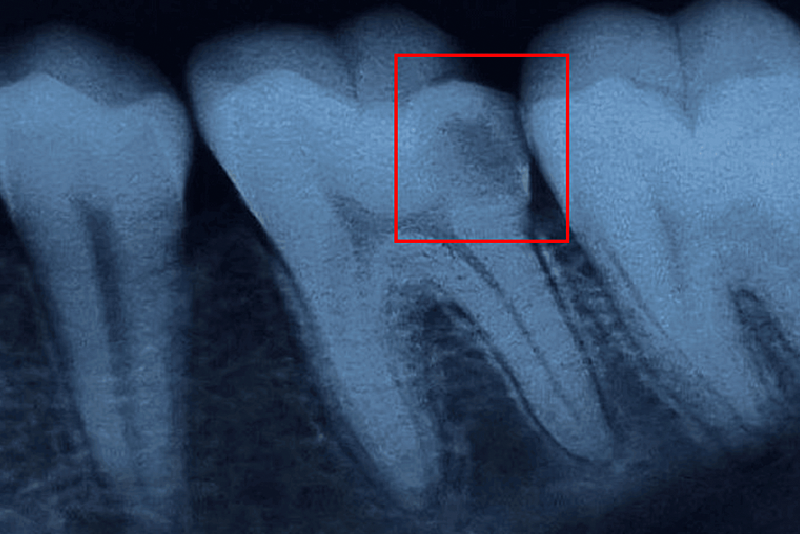

- Chụp X-quang: X-quang nha khoa giúp đánh giá tình trạng viêm có lan rộng hay không và phát hiện các vấn đề khác liên quan đến sức khỏe răng miệng.

Chụp X quang để kiểm tra tình trạng viêm tủy răng